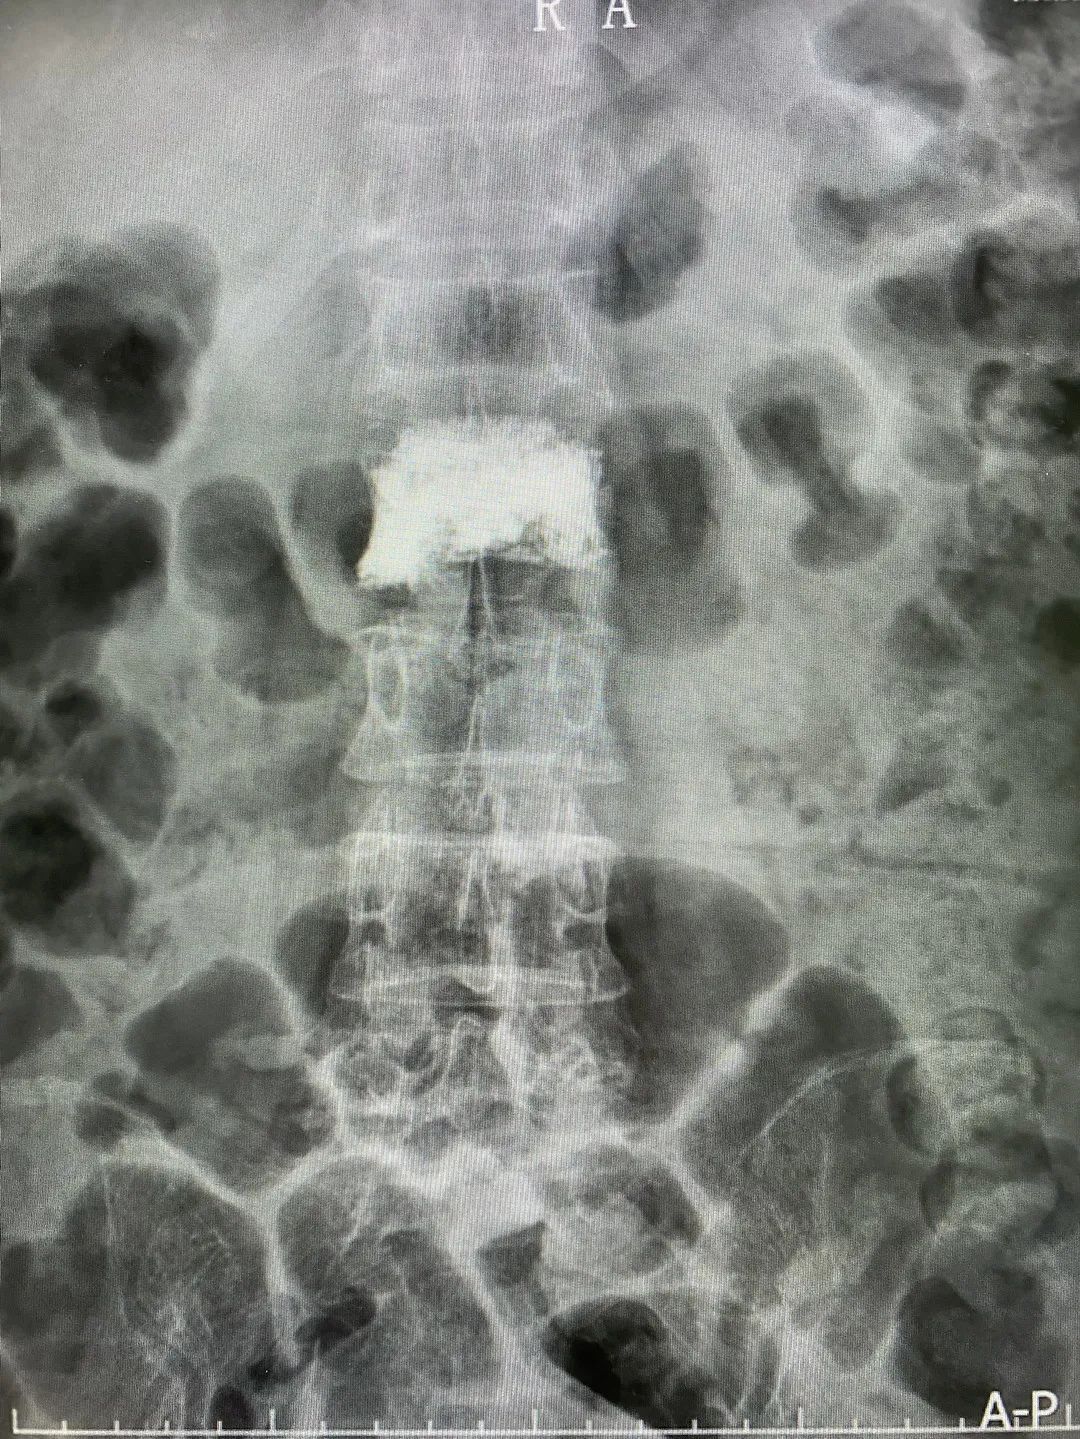

▲既往行椎体成形术后病例,可见腰2椎体术后形态良好,椎体内高密度骨水泥填充,分布均匀无渗漏。